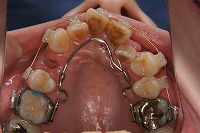

26歳1か月

上顎

前歯が出ていて歯並びが悪い事を主訴に来院された、26歳1か月の女性です。診断「歯と歯槽基底の大きさの不調和による叢生」上顎は右側第1小臼歯と左側の犬歯、下顎は抜歯をせず治療を行いました。